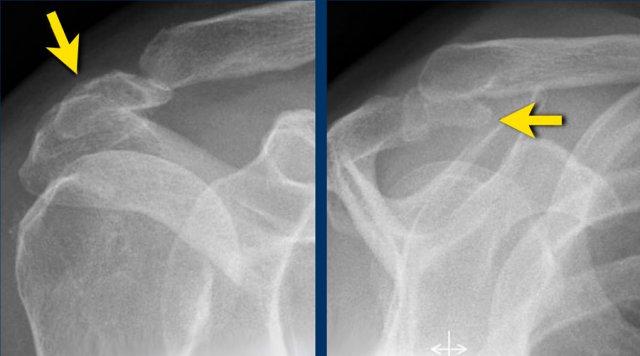

Hình ảnh

Trên chuỗi xung T2W có một tổn thương rách mặt túi hoạt dịch kích thước lớn.

Lưu ý rằng trên MRI khớp có thuốc tương phản từ, tổn thương rách không quan sát thấy do thuốc tương phản từ nội khớp không thể tiếp cận vị trí khuyết trong gân.